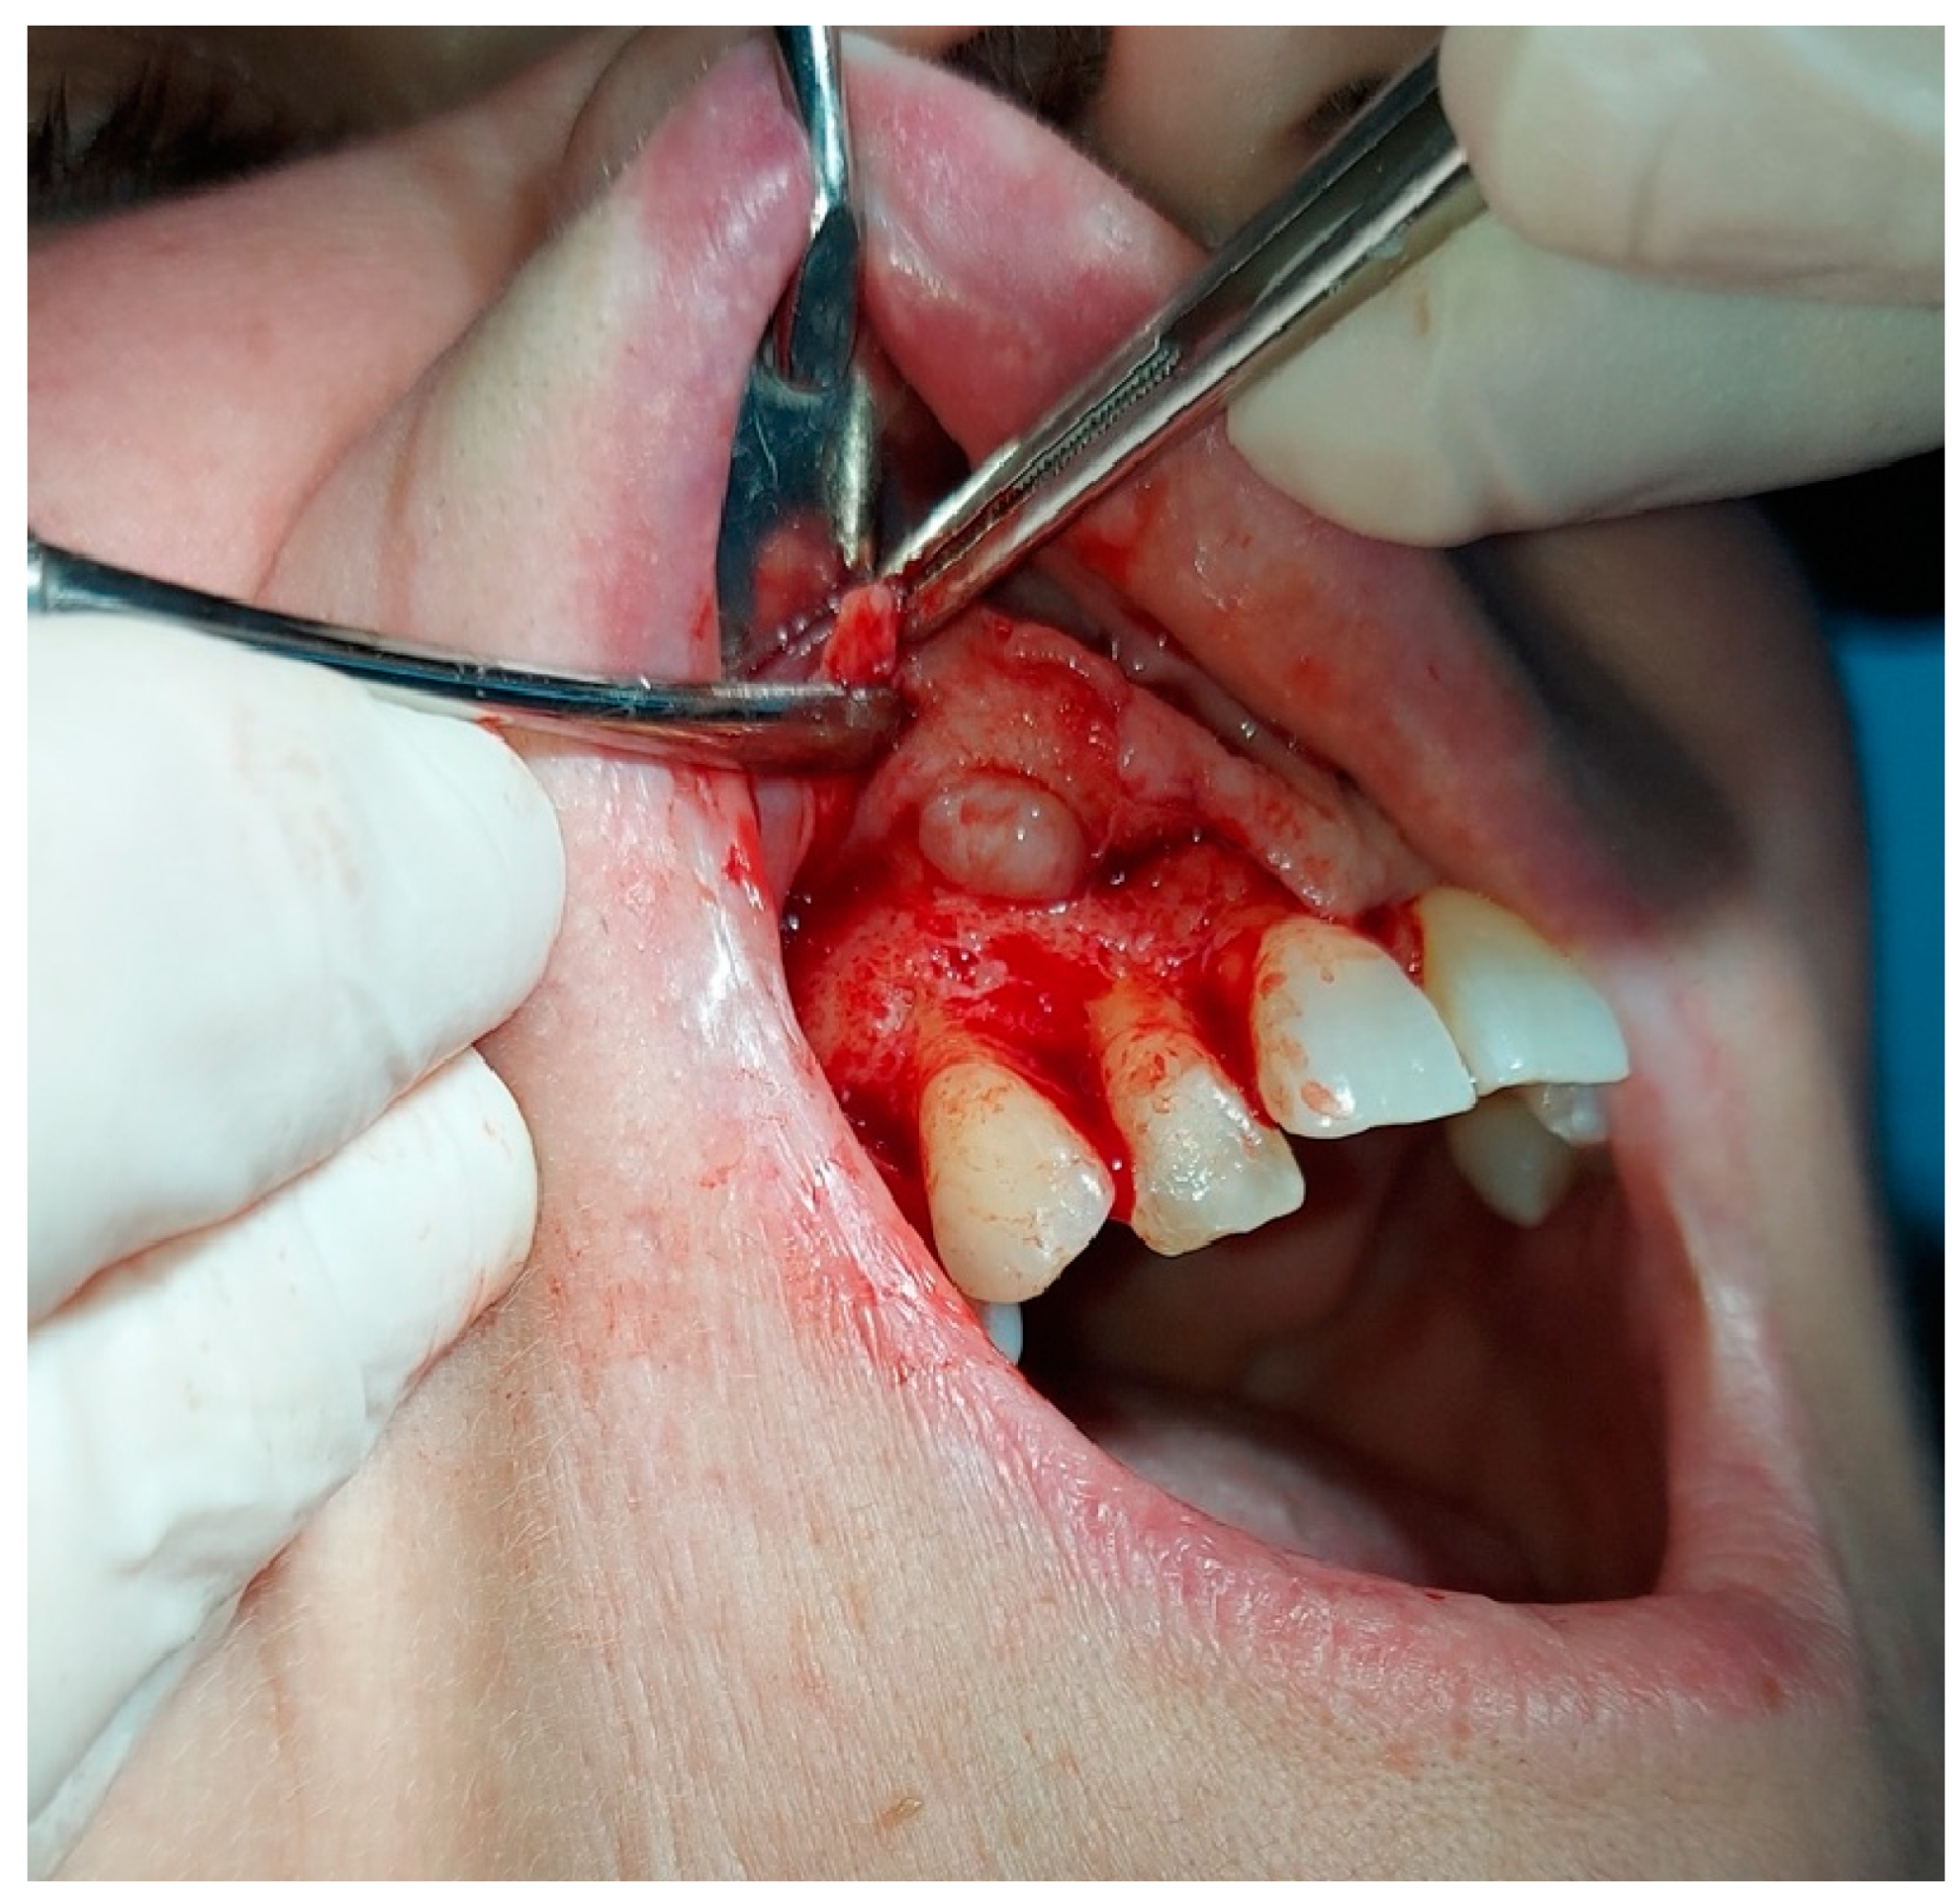

2. The Case